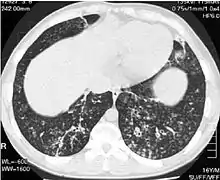

| High-resolution computed tomography images of the lower chest in a 16-year-old boy with diffuse panbronchiolitis | |

The diagnosis of DPB requires analysis of the lungs and bronchiolar tissues, which can require a lung biopsy, or the more preferred high resolution computed tomography (HRCT) scan of the lungs.[7] The diagnostic criteria include severe inflammation in all layers of the respiratory bronchioles and lung tissue lesions that appear as nodules within the terminal and respiratory bronchioles in both lungs.[4] The nodules in DPB appear as opaque lumps when viewed on X-rays of the lung, and can cause airway obstruction, which is evaluated by a pulmonary function test, or PFT.[6] Lung X-rays can also reveal dilation of the bronchiolar passages, another sign of DPB. HRCT scans often show blockages of some bronchiolar passages with mucus, which is referred to as the "tree-in-bud" pattern.[7] Hypoxemia, another sign of breathing difficulty, is revealed by measuring the oxygen and carbon dioxide content of the blood, using a blood test called arterial blood gas. Other findings observed with DPB include the proliferation of lymphocytes (white blood cells that fight infection), neutrophils, and foamy histiocytes (tissue macrophages) in the lung lining. Bacteria such as H. influenzae and P. aeruginosa are also detectable, with the latter becoming more prominent as the disease progresses.[4][5] The white blood, bacterial and other cellular content of the blood can be measured by taking a complete blood count (CBC). Elevated levels of IgG and IgA (classes of immunoglobulins) may be seen, as well as the presence of rheumatoid factor (an indicator of autoimmunity). Hemagglutination, a clumping of red blood cells in response to the presence of antibodies in the blood, may also occur. Neutrophils, beta-defensins, leukotrienes, and chemokines can also be detected in bronchoalveolar lavage fluid injected then removed from the bronchiolar airways of individuals with DPB, for evaluation.[4][9]